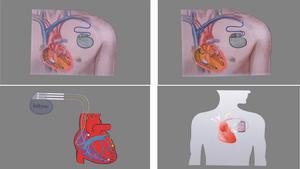

永久性心臟起搏器安裝1.針對原發病積極處理。

2.對雙分支阻滯本身無特殊處理,主要是適時安置人工心臟起搏器。有症狀的雙分支傳導阻滯在下列情況時需安置永久性心臟起搏器:

(1)H-V間期>100ms。

(2)希氏束阻滯伴希氏束波分裂。

(3)心房調搏出現希氏束遠端阻滯。

(4)靜注普魯卡因胺後出現合併左束支末端阻滯或H-V間期>80~100ms。

(5)H-V間期延長,反覆發生暈厥,心內程式刺激未誘發出室性心動過速者。

(6)外科手術引起的右束支阻滯合併左前分支阻滯。原有右束支阻滯,在急性心肌梗死後增加了其他分支傳導阻滯,或新出現的右束支阻滯合併左前分支阻滯,或右束支阻滯合併左後分支阻滯,同時並發一度或二度房室傳導阻滯時,應立即考慮安置臨時心臟起搏器。如經臨時心臟起搏器治療3周后,傳導阻滯仍未能恢復,不能脫離起搏器者,應考慮安置永久性心臟起搏器。